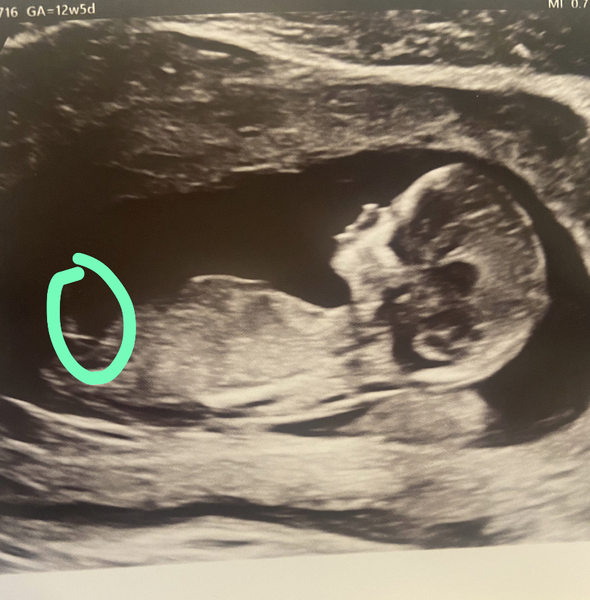

@SantiagoSister they said they could tell us today if we wanted as I think the nub is quite obvious (but I have no idea if I’m looking at the right thing!) but then we chickened out and decided to wait until the 20 week scan.

@Firsttimetrier that’s amazing! You done so well to hold out, I think I might’ve caved 😂🙈 I never have a clue when it comes to nub/skull theories personally! It’ll be a lovely surprise for you in 8 weeks time 😊

I’m going to be controversial and say I think it’s a girl based on the nub theory! 🥰

Oooh that’s interesting @CountryGirl189! I thought this bit I’ve circled was the nub and it looked stacked but I have NO idea what I’m even talking about 😂

If it is a girl, I need to apologise profusely to her when she arrives as I’ve been saying to my husband they have a boy’s face 🤦🏽‍♀️😅